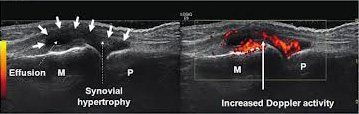

Ευτυχώς τα τελευταία 10-15 έτη έχει σημειωθεί αλματώδης πρόοδος στην Ρευματολογία, τόσο στο διαγνωστικό, όσο και στο θεραπευτικό κομμάτι- δεν είναι τυχαίο ότι μαζί με την Ογκολογία κατέχουν την πρώτη θέση στην εκπόνηση ερευνών παγκοσμίως. Για παράδειγμα, με την χρήση των υπερήχων έχουμε την δυνατότητα πρώιμα και αξιόπιστα να ελέγχουμε αρθρώσεις και περιαρθρικούς ιστούς για φλεγμονώδεις ή/και εκφυλιστικές καταστάσεις, ενώ δίνεται και η δυνατότητα να παρέμβουμε θεραπευτικά με κατευθυνόμενες παρακεντήσεις και εγχύσεις. Επίσης, νεότερα φάρμακα που αναπτύχθηκαν με βάση την κατανόηση των παθογενετικών μηχανισμών των ρευματικών νοσημάτων δίνουν την δυνατότητα για πρώιμη αντιμετώπιση, πριν παρουσιαστούν μη αναστρέψιμες βλάβες.